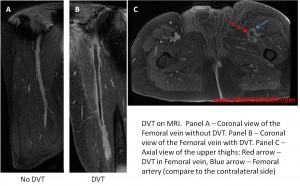

Imaging studies that are used for making the diagnosis of VTE include duplex ultrasound (of the legs), CT angiography / venography, MR angiography and ventilation-perfusion scanning. Although all of these tests are quite accurate, one must move to more imaging studies if there is a high level of suspicion for VTE and one test was negative.

The diagnosis of DVT with duplex ultrasound relies on a combination of three ultrasonographic signs: 1) Direct visualization of the clot, 2) Non-compressibility of the area of the vein where there is clot in the lumen (as seen in the image above in the popliteal vein) and 3) Absence of augmentation when there is clot distal to the area being imaged. These methods may be complemented by color flow duplex that may aid in showing color defects that correspond to clots.